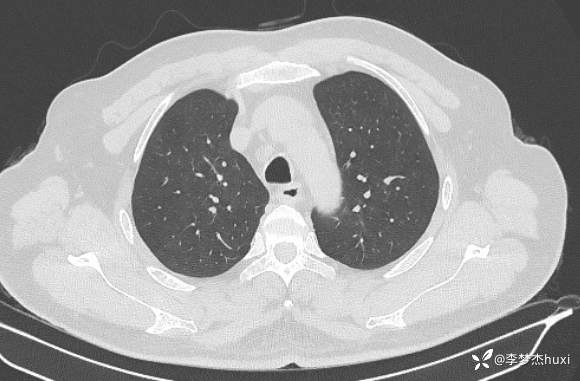

男性48岁,咯血3小时,咯血病因?

主诉:咯血3小时

简要病史:患者于入院前3小时无明显诱因出现咯血,为鲜红色,量较多,约10ml,伴胸闷、压气,伴咳嗽,无明显咳痰。

体格检查:T36.2℃,P110次/分,R20次/分,BP250/130mmHg。神清,呼吸平稳,浅表淋巴结不大,双肺叩清音,双肺未闻及干湿性啰音,心率110次/分,律齐,无杂音。腹部平坦,软,全腹无压痛,无反跳痛及肌紧张,肝脾肋下未触及,双下肢无水肿。

辅助检查:胸部CT:双肺炎症,双肺纹理增多,主动脉及冠状动脉钙化,主肺动脉稍增粗,右侧肾上腺点状高密度影,考虑脂肪肝。

临床诊断:肺炎咯血